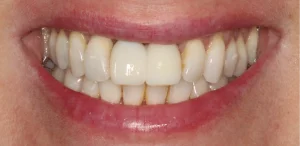

This lady was very upset after a dumbbell hit her mouth in the gym and knocked the front tooth out.

A temporary bridge was made to avoid her having to wear a temporary denture during the teatment, which is less comfortable.

A single implant with bone grafting was placed.

Once the implant was bedded into the bone, a new porcelain crown was fitted on the implant, and a new crown was placed on the adjacent tooth to match in better.